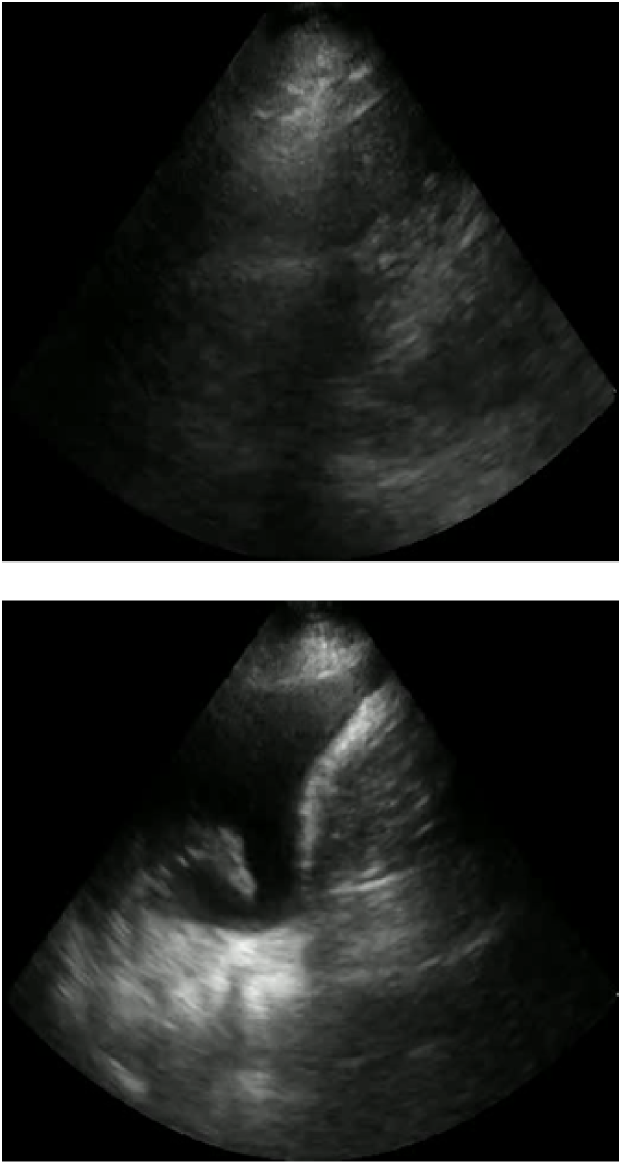

The LUS interpretative workflow addressed in this work has been described as a decision tree [19]. After determining the view, the interpreter traverses down the tree to look for increasingly specific artefacts that reduce a possible differential diagnosis. We focus on three binary classification tasks for LUS image interpretation: view classification (View), A-line versus B-line classification (A/B), and pleural effusion detection (PE). The former is applicable to parenchymal LUS views, and the latter to pleural LUS views. Table 1 summarizes these tasks, and Figure 1 displays emblematic examples for each class.

Refer to caption

(a) View: Parenchymal (top), pleural (bottom)

(b) AB: A-lines (top), B-lines (bottom)

(c) PE: No PE (top), PE (bottom)

Figure 2: Examples of each class for each LUS binary classification task: View (a), AB (b), and PE (c).